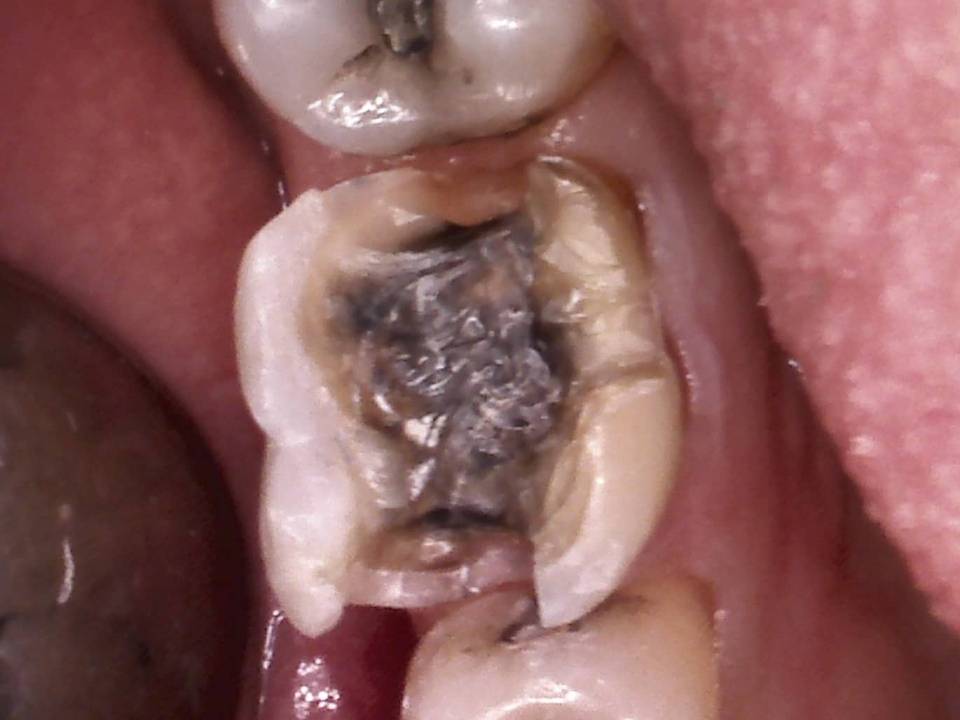

Ist der Defekt zu tief oder der Nerv im Zahn abgestorben, ist vorher eine Wurzelkanalbehandlung notwendig. Dabei wird der Hohlraum im Zahn gesäubert, desinfiziert und anschließend mit Guttapercha versiegelt. Das Ganze erfolgt in unserer Praxis in der Regel mittels moderner maschineller Aufbereitung und durch suffiziente Lokalanästhesie können unnötige Schmerzen verhindert werden.